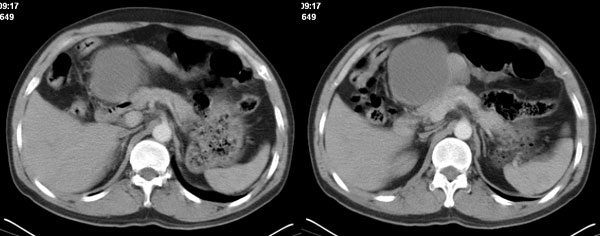

李**,男,46岁,便血1天入院,慢性贫血貌,腹平、软,剑突下压痛,肠鸣音稍活跃,hb大于1g/l,胃镜:慢性浅表性胃炎,b超:1肝内多发性占位 2腹腔内囊性肿块 ,肝内圆形影平扫ct值42.9,动脉期48.6,静脉期58.2,延迟期62.2

影像学表现:1 腹腔前中部、胰腺前方囊实性病灶(个人认为确定有否实性成分存在这是关键,涉及到鉴别诊断,如果是口服阳性造影剂则可明确左侧是不是小肠了),囊性部分囊壁不均,实性部分有强化,与小肠关系较密切,局部小肠受推移;与胰头、胃后壁均有脂肪间隙存在;2 胰腺无异常改变,胰周无渗出;3肝后段包膜下2个小圆形低密度灶,从图像和楼主提供的ct值来看有轻度强化,灶周无片状强化,不似单纯囊肿及肝癌、炎性病变表现;4 腹膜后及腹腔内无淋巴结肿大。

分析:1 如果腹腔内是囊实性病灶,则应多考虑肿瘤性病变,如源于小肠的间叶源性组织如神经源性肿瘤或间质瘤等;如果这么大存在恶性变的可能,那么肝内则可考虑为转移,征象亦符合;这种可能性最大;

诊断:小肠间叶组织源性肿瘤如神经源性肿瘤或间质瘤恶性变伴肝内转移可能性最大,不除外先天性胆管囊肿。

胰腺边界清晰,胰周筋膜不厚,胰周脂肪密度无明显增高;其前方囊实性病灶,边界清晰,增强后实性部分轻度强化;肝内多发边界清晰低密度影,增强后无明显强化(平扫ct值42.9,动脉期48.6,静脉期58.2,延迟期62.2)。

考虑:胰腺囊腺瘤,肝内小肝癌可能大。

原因:胰头前方,前上腹部巨大囊实性肿物,与小肠关系密切,与胰头及胃壁之间脂肪间隙存在,囊壁不均匀,部分强化,占位效应明显,小肠上段扩张,十二指肠及胃腔内大量食物存留,说明上消化道有部分梗阻。因此,考虑来源于肠道的肿瘤。再结合其病史及肝内改变,这样考虑更有道理。

我们先确定病变来源于何处。从片上看,应该说是起源于肠道的囊实性的肿块。二、肝内低密度影,增强强化随时间强化,考虑小血管瘤。